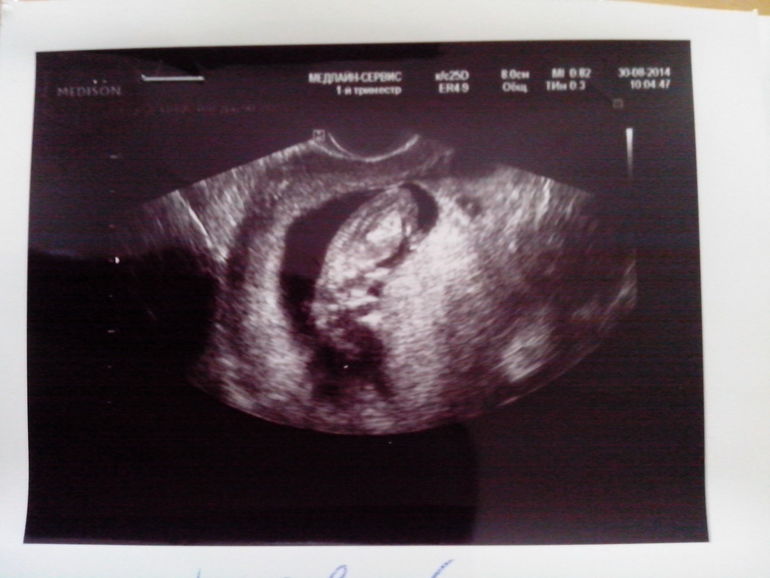

63d284feaff529d001f502a8a762566f.jpgЭто правый ляль, от левого видно кусочек домика 8629a16141a7a6b745bbb2f309087a58.jpgА это левый :-)  видно кусочек домика правого :-))) это ее снимки вчерашние!!

Да!!! Видно перегородку и она очень хорошая!!! Может она описалась! Ну в любом случае у вас как и у нас Ди Ди!

544fe521bbf18c0a36f7d188dc112972.jpgЭто где-то 8 недель, в правом на этом снимке фасолинку не видно, только домик... Моно ди не могут же быть таак далеко др от друга. В 5 недель они были еще дааальше друг от друга

Чуть выше прикрепила фото, очевидно же, что попутать тип вряд ли могли. Они так далеко др от друга